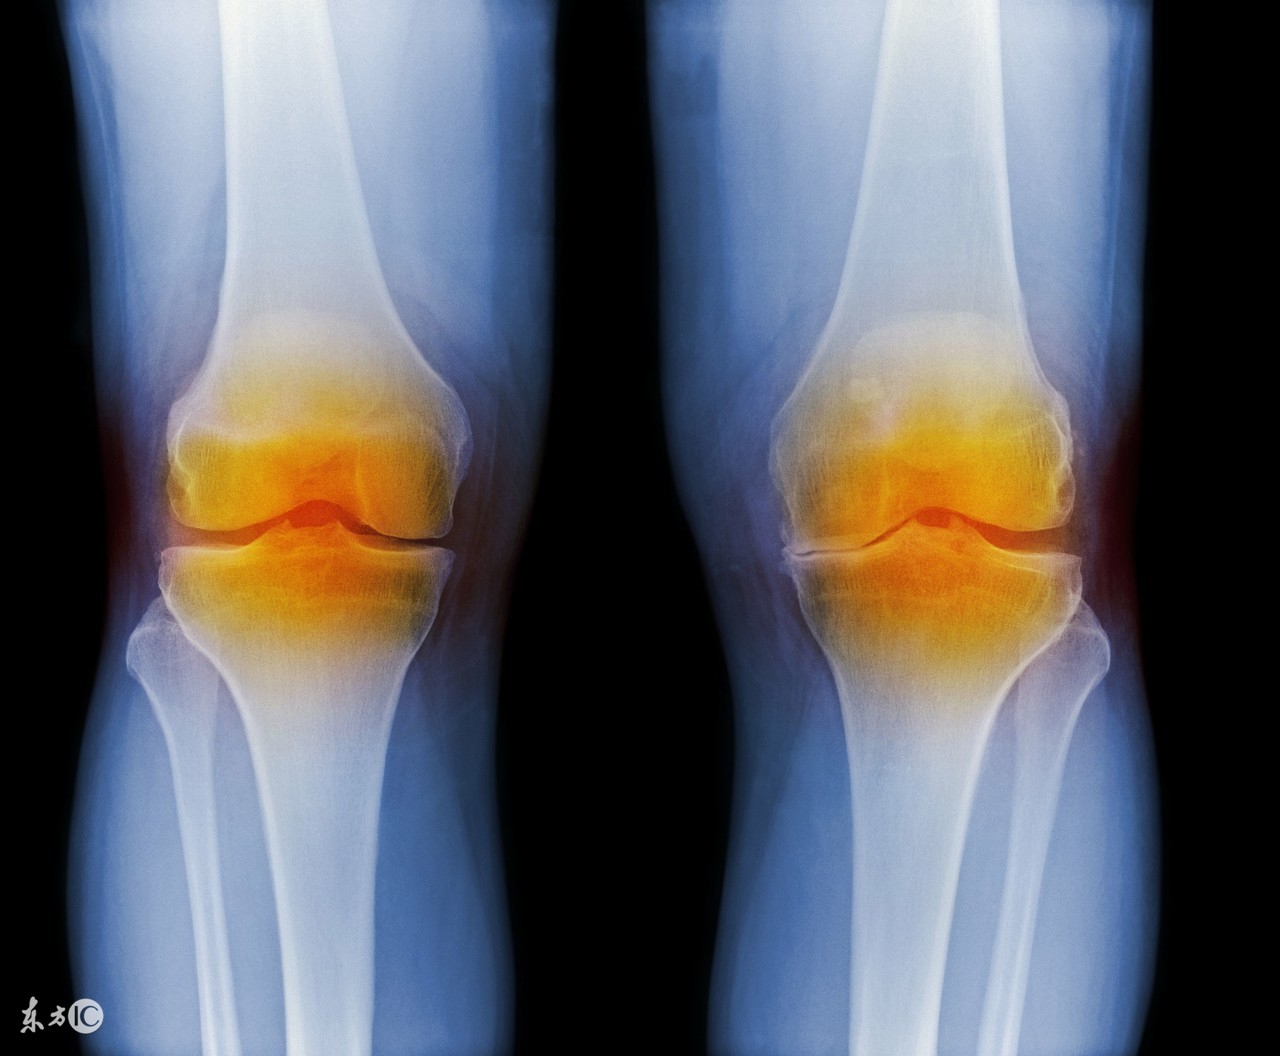

李:KOA其实是因膝关节的承重及磨损导致的软骨损伤及缺失,进而出现软骨下骨硬化、囊变、骨髓水肿,因应力改变而导致骨赘形成的一种无菌性炎症。

关节磨损 膝关节按其解剖学形态分为三个间室,分别为内侧胫股间室、外侧胫股间室、髌股间室。关节磨损最常先累及前内侧间室,由于其内翻畸形,内侧副韧带受损,关节稳定性降低,这时候就从前内侧间室OA演变成内侧间室OA,磨损日久,前交叉韧带也会断裂,逐渐进展为多间室OA甚至全膝的OA。

这两者在疾病的进程中,往往同时伴行又相互促进。关节磨损以后还会出现关节松动,为了稳定关节或者是受力增加的缘故,在韧带附着部位出现骨质增生或骨刺,关节软骨和半月板的进一步磨损、丧失,出现关节间隙狭窄、变形、滑膜炎,最终形成KOA。

李:首先,有一定的临床症状和体征:①关节疼痛及压痛:初期为轻度或中度间断性隐痛,休息时好转,活动后加重,疼痛也经常与天气变化有关。晚期可出现持续性疼痛或夜间痛。关节局部有压痛,在伴随有关节肿胀时尤为明显。②关节僵硬:在早晨起床时关节僵硬及发紧感,也称为晨僵,活动后可缓解。关节僵硬在气压降低或空气湿度增加时加重,持续时间一般较短,常为几分钟至十几分钟,很少超过30分钟。③关节肿大:手部关节肿大变形明显,可出现Heberden 结节和 Bouchard 结节。部分膝关节因骨赘形成或关节积液也会造成关节肿大。④骨摩擦音( 感): 由于关节软骨破坏、关节面不平,关节活动时出现骨摩擦音( 感) ,多见于膝关节。⑤关节无力、活动障碍 关节疼痛、活动度下降、肌肉萎缩、软组织挛缩可引起关节无力,行走时软腿或关节绞锁,不能完全伸直或活动障碍。那我们在临床诊断时也会综合临床表现,实验室及X线检查来确诊KOA。